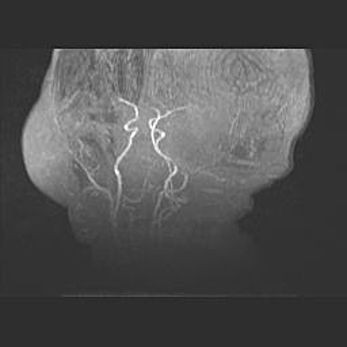

Церебральная ишемия II.

Возраст: 5 дней

Вес: 3400 г

Пол: женский

Окружность головы: 35 см

Срок гестации: 39 недель

Церебральная ишемия – это заболевание, характеризующееся недостаточностью (гипоксией) либо полным прекращением (аноксией) снабжения мозга кислородом по причине закупорки одного или нескольких сосудов. Это приводит к  что метаболическим расстройствам различной степени тяжести в тканях головного мозга, развитию коагуляционных некрозов и гибели нейронов.